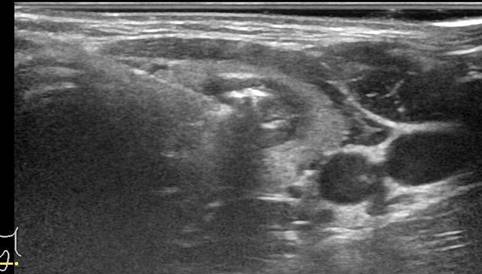

(Ảnh: siêu âm bệnh nhân sau khi tiêm cồn điều trị nang giáp trái

(Ảnh: Bệnh nhân sau khi tiêm cồn điều trị nang giáp trái)

Sau khi điều trị, khối sưng vùng cổ của bệnh nhân gần như không còn nhìn thấy, không để lại sẹo, bệnh nhân có thể ra về luôn, bệnh nhân được hẹn tái khám, theo dõi tổn thương sau một tháng, hầu hết đối với các nang giáp chảy máu sẽ rất hiệu quả khi làm PEI.